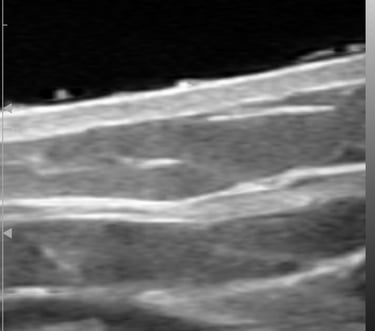

Ecografía cutánea de alta frecuencia